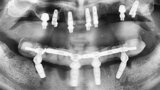

Kombinace standardních a ultrakrátkých implantátů při rehabilitaci celých úst